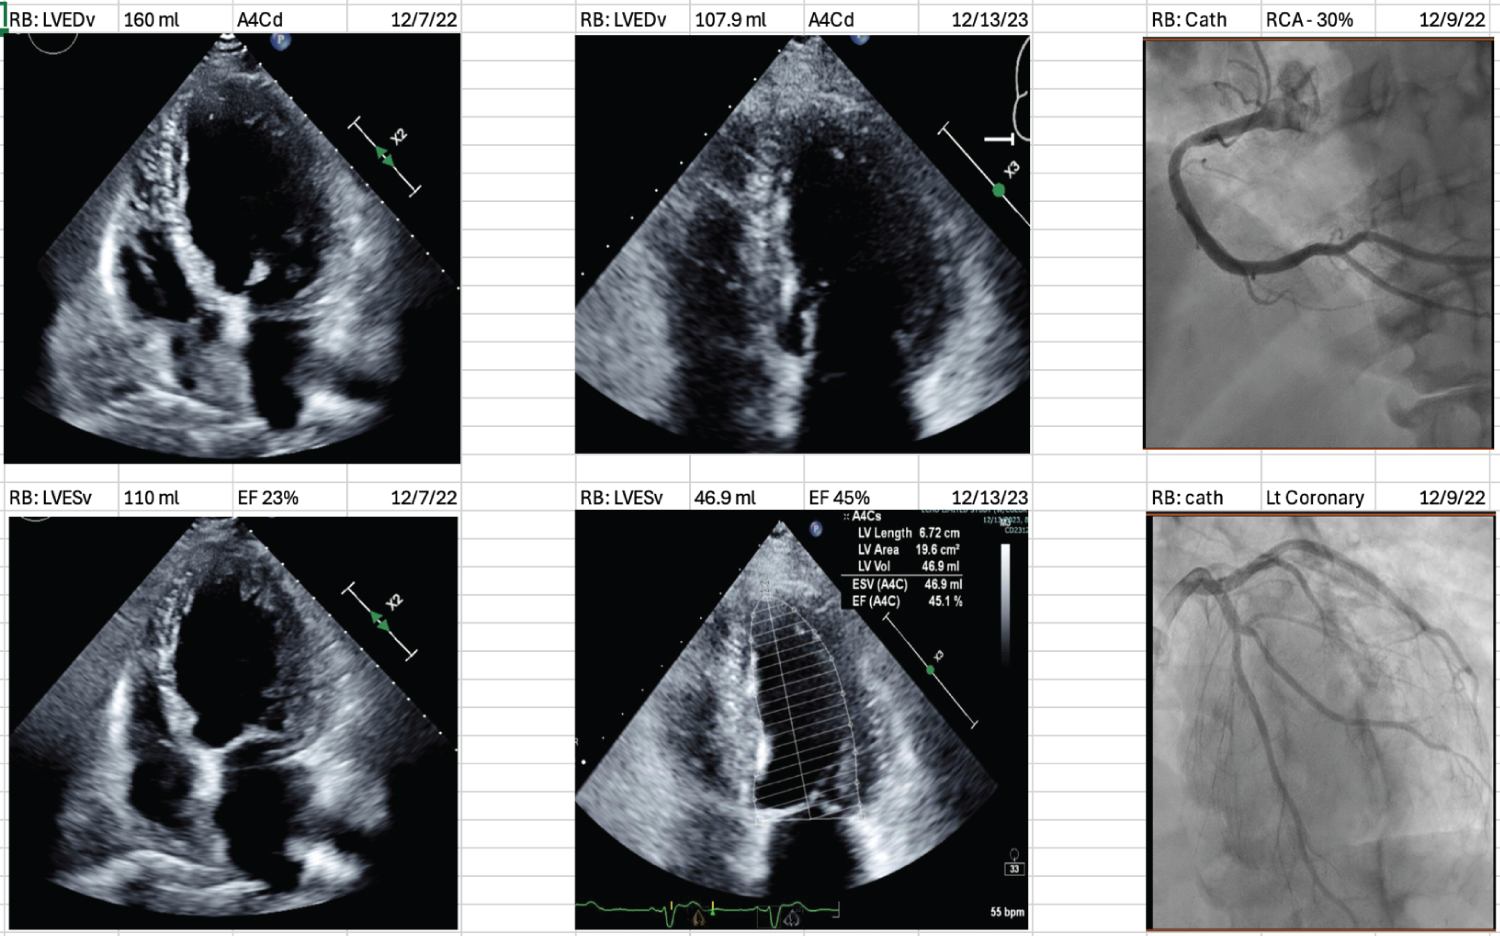

A case of NICM is illustrated with the left ventricular echocardiographic findings before treatment (baseline) and after treatment (final), along with the coronary angiography at baseline in Figure 3.1. Similarly, a case of ICM is illustrated in Figure 3.2.

Figure 3.1: A case of nonischemic Cardiomyopathy (NICM).

Echocardiograms: Left panel- upper as baseline (before treatment) LVED volume in diastole and the left lower as LVED volume in systole; Middle panel- upper as final (after treatment) LVED volume in diastole and the lower middle in systole (apical 4C views).

Coronary angiograms: Upper right: RCA has 30% proximal narrowing. Lower right: The left coronary arteries have only minor narrowing. View Figure 3.1